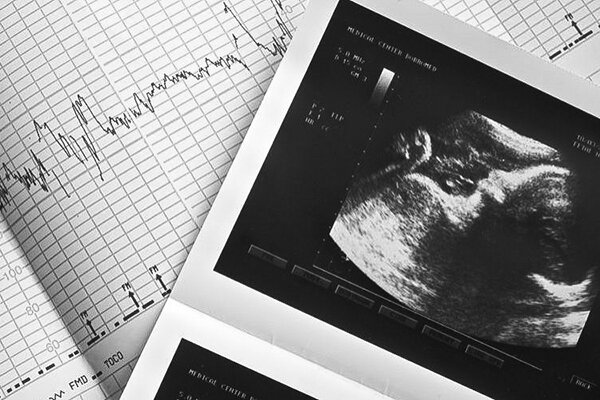

به گزارش خبرگزاری ایمنا و به نقل از پایگاه اطلاع رسانی دولت، مرضیه وحید دستجردی با اشاره به موضوع غربالگری گفت: غربالگری امروز در کشور ما انجام می شود و منعی برای انجام آن وجود ندارد.

وی با تاکید بر اینکه البته عده ای سعی کردند در قانون منع ایجاد کنند، افزود: با پیگیری های انجام شده توسط متخصصان زنان این اتفاق نیفتاد و غربالگری همچنان انجام می شود و حتی در قانون وجود دارد؛ اما در صورت عدم رعایت قوانین و مقررات مربوط به این امر، این امر محقق نشد. بنابراین منعی در این زمینه اعمال نشد و غربالگری در کشور انجام می شود.